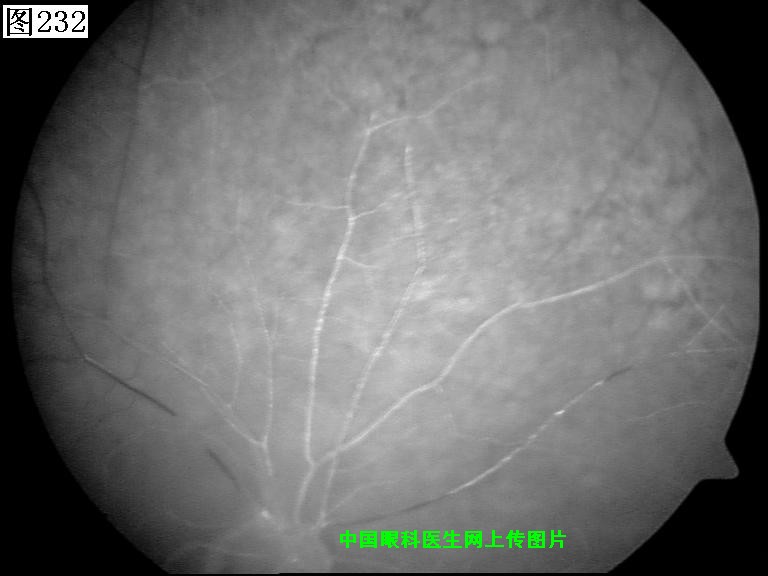

229 230 231 232